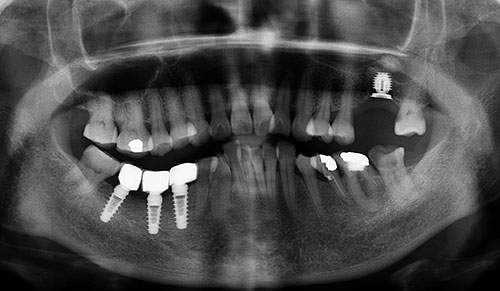

家住福州台江的李阿姨,在去年一家口腔医院做过一颗种植牙,可是近出现牙体松动,牙齿还有一点痛的症状,饮食生活都受到影响,福州贝臣齿科医生为李阿姨拍全景CT检查后,发现李阿姨在做种植牙时,医院未严格遵循种植牙外科原则进行手术,种植牙手术的创伤过大或在愈合阶段骨膜穿孔,造成种植牙不良愈合。那么种植牙后出现松动还有哪些原因呢?应该怎么应对这种情况呢?福州贝臣齿科医生为大家详细介绍! 点击免费咨询,或者拨打24小时牙齿健康热线0591-88681777咨询,贝臣齿科医生为您解答!

福州贝臣齿科医生介绍说,种植牙松动的原因可归结为手术问题和牙体质量问题的。手术问题主要是因为未严格遵循种植外科原则进行手术,手术的创伤过大或在愈合阶段骨膜穿孔,造成不良愈合。由于手术过程中没有很好的冷却水降温,未能把温度控制在47℃以下,长时间的较高温度造成骨细胞死亡,从而不能形成骨愈合,种植体植入后由于手术的原因造成种植体早期微动,因而无法形成骨愈合。

至于牙体质量的问题可归结为修复体设计不合理,制作时未能达到要求的精度,局部造成过重负荷,造成种植体周围的骨质发生细微骨折,或修复体精度不够,完成修复后,有较大的应力作用于种植体上,发生骨吸收,还可能因持续性牙龈炎、种植体周围炎、牙合力分布不均匀,导致种植部位发生进行性骨吸收。